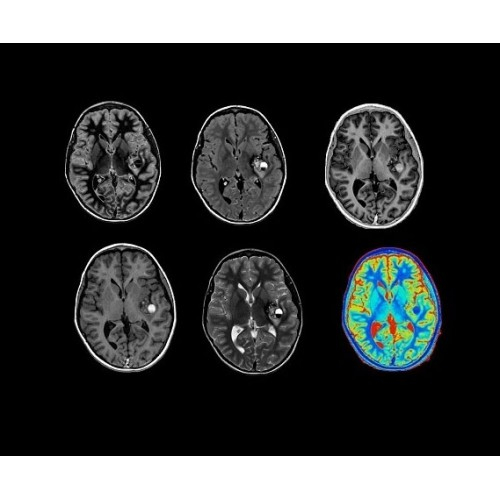

SIGNA PET/MR 3.0T — это гибридная система, в которой совмещаются две принципиально разные технологии — магнитно-резонансную томографию (МРТ) и позитронно-эмиссионную томографию (ПЭТ). Система отличающийся высокой чувствительностью и эффективностью и предназначена для диагностики в области онкологии, неврологии, кардио-васкулярных исследований, исследований воспалительных процессов.

Компания GE Healthcare представляет революционную, полностью интегрированную систему SIGNA PET/MR1, в которой сочетаются времяпролетная технология (TOF) и возможности напряженности магнитного поля 3.0 Тл. Мы поможем вам поднять исследования на более высокий уровень. SIGNA PET/MR позволяет достичь впечатляющей точности и скорости исследований, а благодаря новейшей технологии реконструкции Q.Clear2 качество изображений улучшается в два раза. Кроме того, в систему включен полный набор клинических приложений и гибких катушек для проведения любых видов исследования, открывая для вас возможности визуализации, о которых вы даже не догадывались.

В систему SIGNA PET/MR встроены запатентованные детекторы кремниевого фотоумножителя (SiPM) и сверхчувствительные кристаллические сцинтилляторы на основе лютеция толщиной 25 мм. Благодаря этому обеспечивается исключительная чувствительность и возможность использования времяпролетной диагностики (TOF).

Кроме того, в результате использования технологии TOF и инновационной технологии реконструкции Q.Clear вы сможете добиться прекрасного соотношения сигнал/шум. А благодаря технологии нулевого времени эхо (ZTE) визуализировать костную структуру без ионизирующего излучения. Все эти разработки для улучшения качества сканирования и точности анализа помогут вам использовать весь потенциал ПЭТ/МРТ.

Впечатляющие клинические возможности

Система SIGNA PET/MR предлагает впечатляющие клинические возможности и открывает доступ к наиболее полным пакетам программных приложений.

• TurboTOF — инновационная технология позволяет корректировать коэффициент затухания сигнала и минимизировать потери анатомических данных, создавая МР-систему для количественной визуализации.

• Q.Clear — в основу технологии легли накопленные знания о том, как минимизировать помехи при реконструкции и получить четкое изображение. При значительном улучшении качества изображения сохраняется точность расчетов. Сочетание технологии TOF и реконструкции Q.Clear — ваш надежный помощник для получения точных и достоверных данных.

• МРТ с функцией нулевого времени эхо (ZTE) отличается точностью, возможностью персональных настроек и отсутствием ионизирующего излучения. Она приходит на смену традиционному исследованию на основе рентгеновского излучения. МРТ с функцией нулевого времени эхо (ZTE) на базе SIGNA ПЭТ/МРТ является более надежной и быстрой по сравнению с системами, использующими сверхмалое время эхо (UTE).

• Специальный пакет приложений для измерения и сравнения объемных изображений ЦНС с нормами поможет вам в диагностике нейродегенеративных заболеваний, а дополнительные инструменты визуализации — в постановке точного диагноза с помощью бета-амилоидов и радиоизотопных маркеров ФДГ.